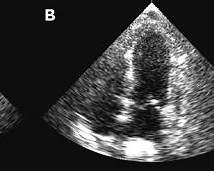

Diagnosis is based on clinical presentation, ECG changes, modest troponin elevation, echocardiographic regional wall motion abnormalities beyond a single coronary territory, absence of obstructive coronary disease, and supportive cardiac MRI findings.

5 Cardiac MRI in Takotsubo cardiomyopathy most commonly shows which finding?

Explanation:

Takotsubo cardiomyopathy shows myocardial edema without infarction-type scar on MRI.